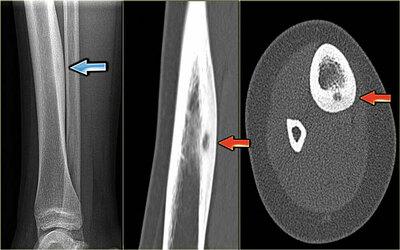

- при поражениях конечностей заболевание отражается на походке человека, при двигательной активности усиливается болевой синдром, отдающий на мышечный аппарат;